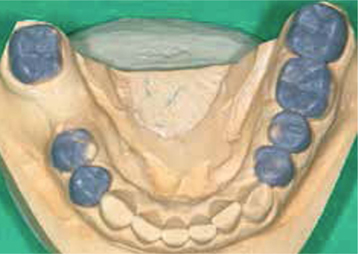

Tijdelijke fase (november en december 2010)

In de tijdelijke fase begonnen we met het vervaardigen van een mock-up in het front om de lengte van de nieuw frontelementen te bepalen (afbeelding 16 ). Tevens voerden we een esthetische facebow en beetbepalingen uit. Ook werden de esthetische en fonetische checklists ingevuld. Hiervoor gebruikten we de lijsten zoals die zijn opgesteld door Mauro Fradeani. Deze lijsten worden bij zijn boek The esthetic rehabilitation in fixed prosthodontics - vol 1 geleverd. Al deze informatie werd, samen met de overige informatie uit de aanvullende onderzoeken en met een paar nauwkeurige afdrukken (Impregum, 3M Espe) aan de tandtechnicus gegeven voor het vervaardigen van een set-up in was (afbeelding 17 en 18 ) en de bijbehorende mallen.

Afb. 18

Set-up in was van de onderkaak.